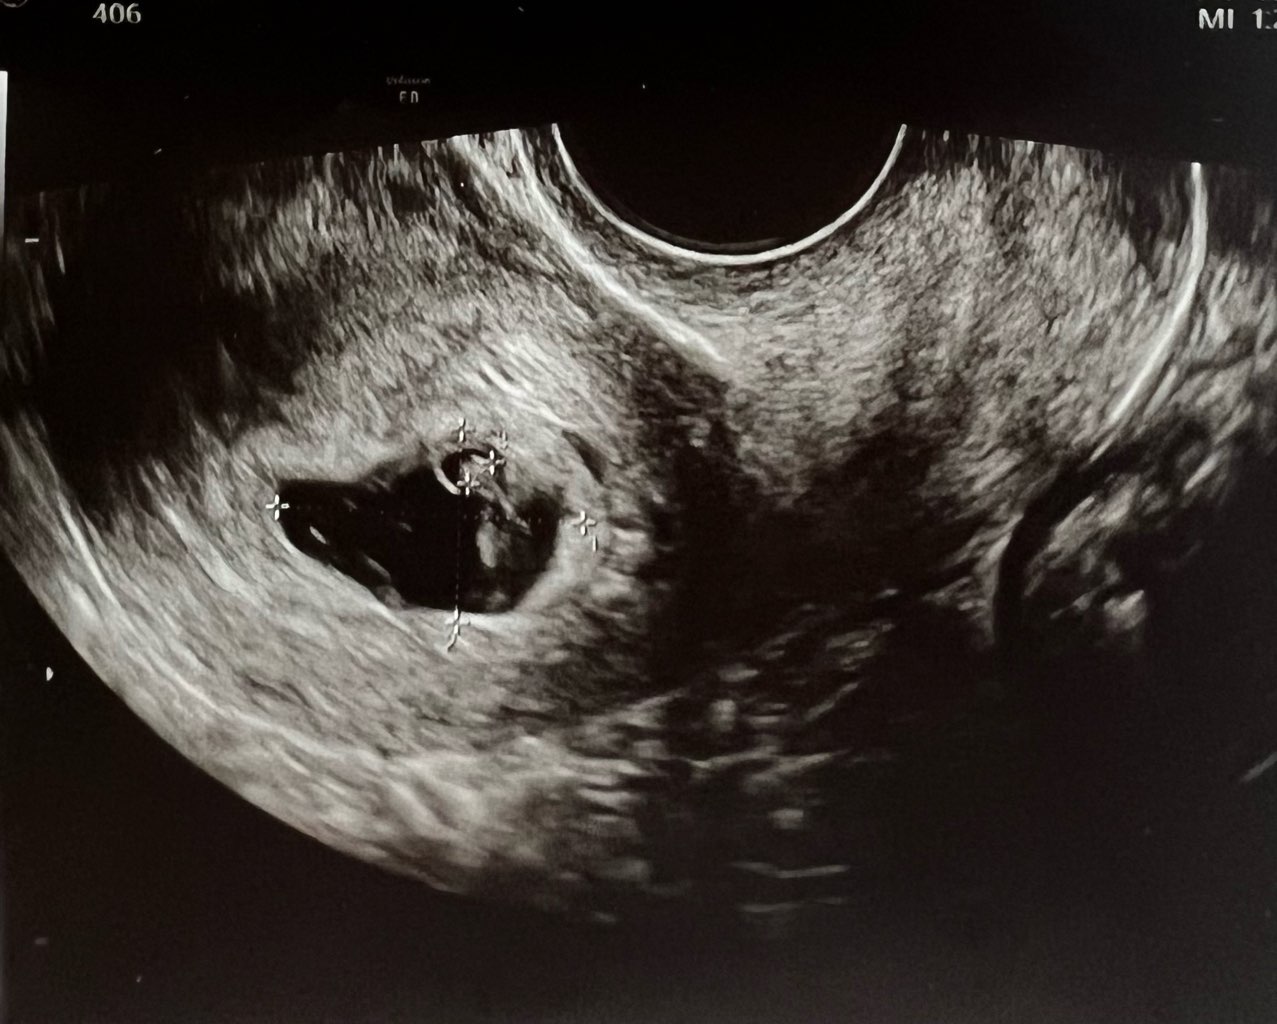

Czy któraś z Was miała podobny pęcherzyk?

Lekarz stwierdził tylko, ze nie wie co ma o tym myśleć… bo jest duży i nieregularny…

Mam krwiak 17mm, raz poleciała mi krew, ale serduszko zaczęło bić.

2 tyg temu pęcherzyk ciążowy był okrągły, a teraz jest taki dziwny

6t4d, CRL 0,67cm, biorę luteinę i neoparin